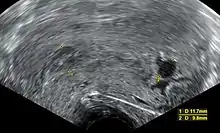

| An ultrasound showing a gestational sac containing a yolk sac but no embryo. | |